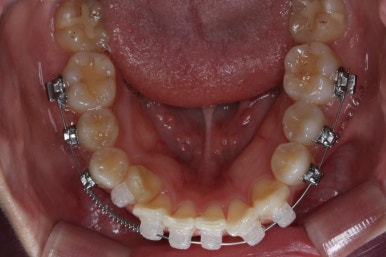

아랫니에도 이제 장치를 붙였습니다.

과개교합인 채로 아랫니에도 장치를 붙이게 되면 아랫니 장치가 깨물려서 다 떨어지거나 부서지기 쉽습니다. 따라서 바이트터보는 굉장한 역할을 하게 됩니다.

눈으로 보기에는 과개교합이 개선이 된 것처럼 보이지만 아직은 아닙니다. 바이트터보가 남아있는 채로도 어금니가 맞물려야 진짜로 개선된 것이죠.

아랫니도 어느 정도 많이 가지런해졌습니다.

이제 아래쪽도 당겨 넣습니다.

원하는 만큼, 허락하는 만큼 계속 당겨 넣습니다. 연산동교정치과에서는 비발치 돌출입 교정을 위해 총 4개의 미니스크류를 식립했습니다.